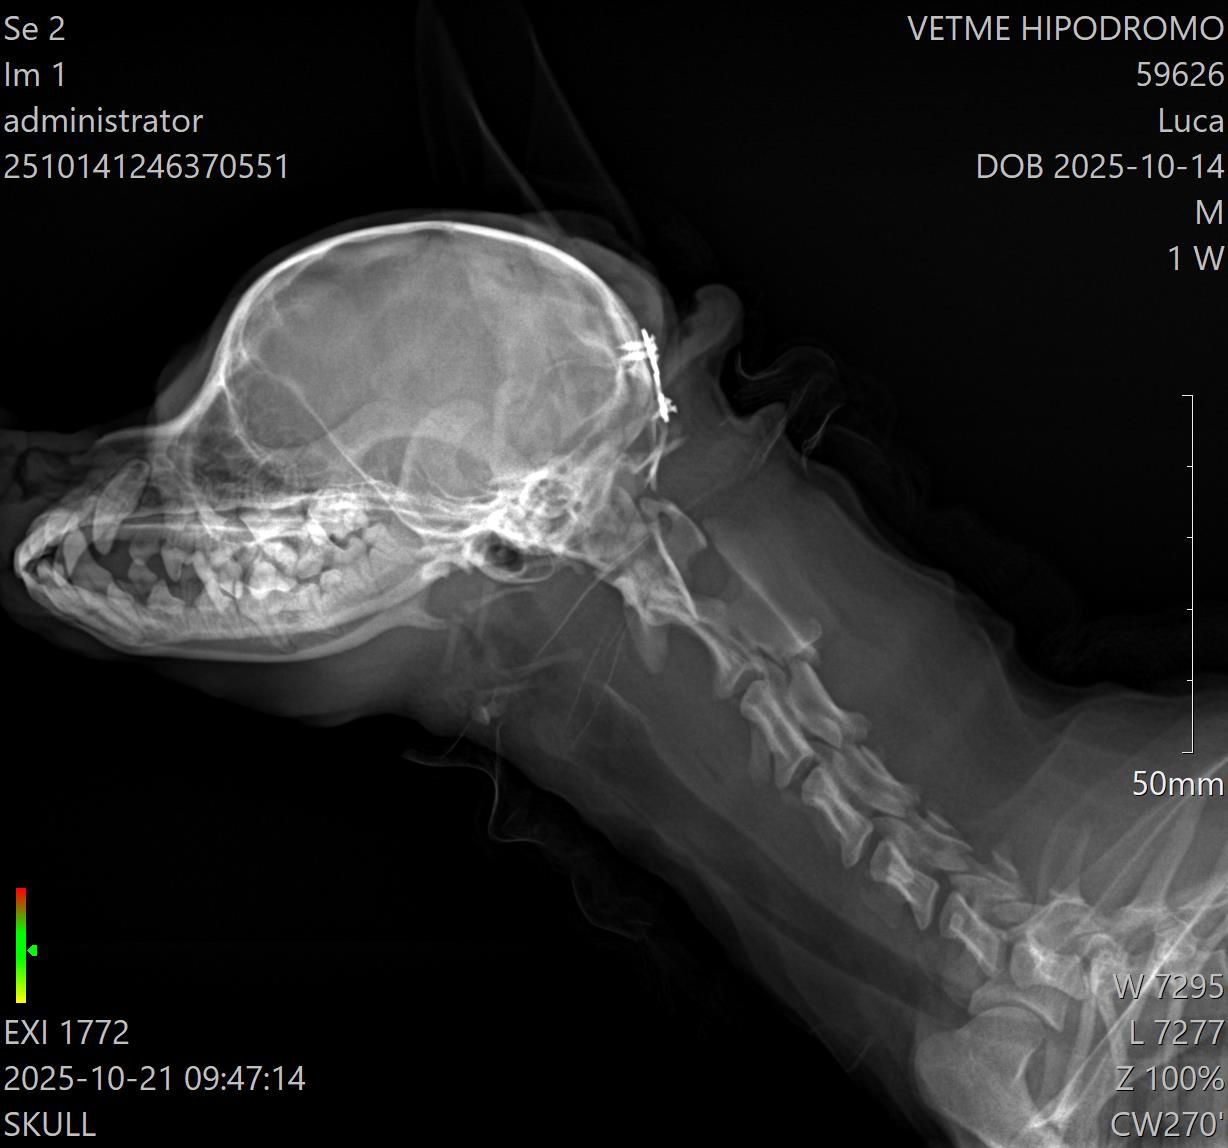

Rayos X y Ultrasonido

Dentro de CENEV contamos con especialistas dedicados al área de imagenología, dedicados al diagnóstico por pruebas como ultrasonido abdominal, radiología de tórax y abdomen, entre otras.

Nuestros equipos y personal especializado permiten estudios rápidos y de alta calidad para apoyar el diagnóstico clínico.